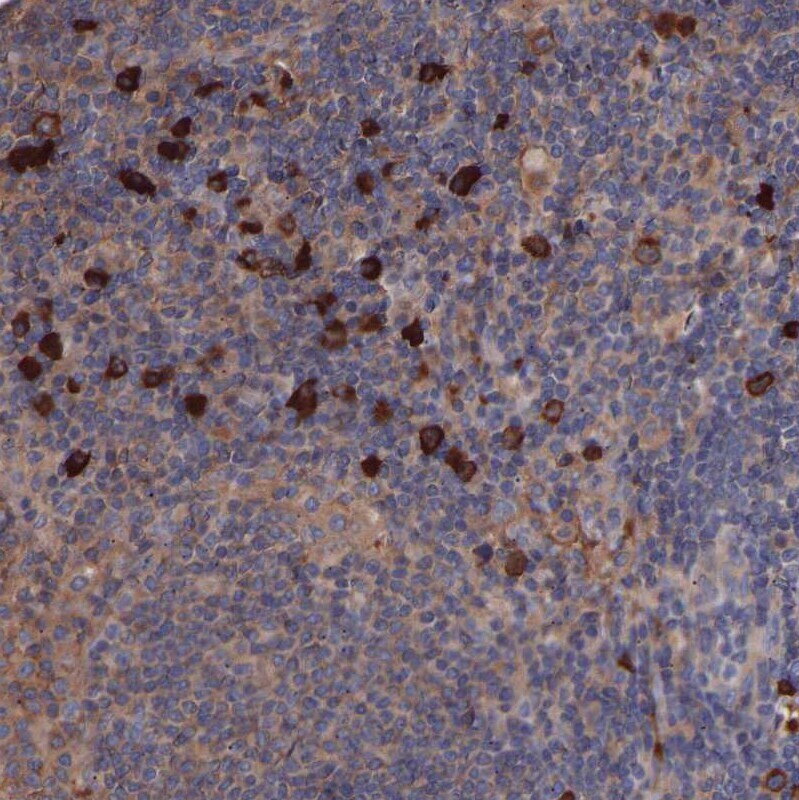

- Immunohistochemical analysis of CI091 in human lymph node using CI091 Polyclonal Antibody (Product # PA5-53560) shows strong cytoplasmic/ membranous positivity in a small subset of lymphoid cells.